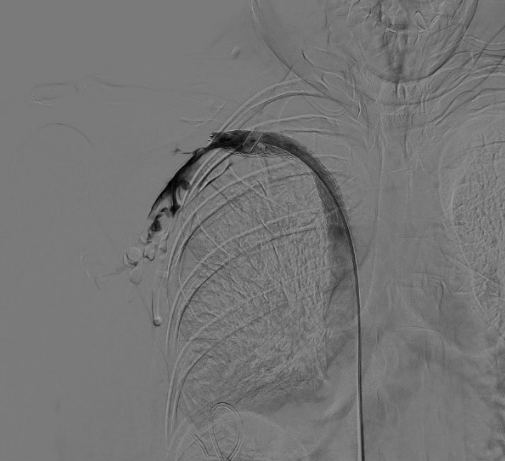

術(shù)后

經(jīng)過測量確定優(yōu)先使用球囊進行狹窄段靜脈預(yù)擴張,在韋運豪主治醫(yī)師、熊偉主治醫(yī)師及朱海副主任醫(yī)師的合作下對閉塞段血管反復(fù)擴張數(shù)次,再次造影見閉塞段血管較前改善,但靶血管區(qū)狹窄程度仍約80%,根據(jù)國內(nèi)外專家指南共識,當經(jīng)皮腔內(nèi)血管成形術(shù)(PTA)后閉塞血管段發(fā)生彈性回縮或殘余狹窄>30%時,具有進一步行支架置入術(shù)干預(yù)的指征。

DSA引導(dǎo)下精準定位釋放支架成功,再次造影,頭臂靜脈閉塞段開通,血流可順利回流至上腔靜脈,但右側(cè)鎖骨下靜脈遠心端及腋靜脈可見血栓形成,遂予以留置導(dǎo)管溶栓治療。

術(shù)后3h,患者右上肢皮膚張力明顯緩解,術(shù)后24h,右上肢腫脹明顯緩解。